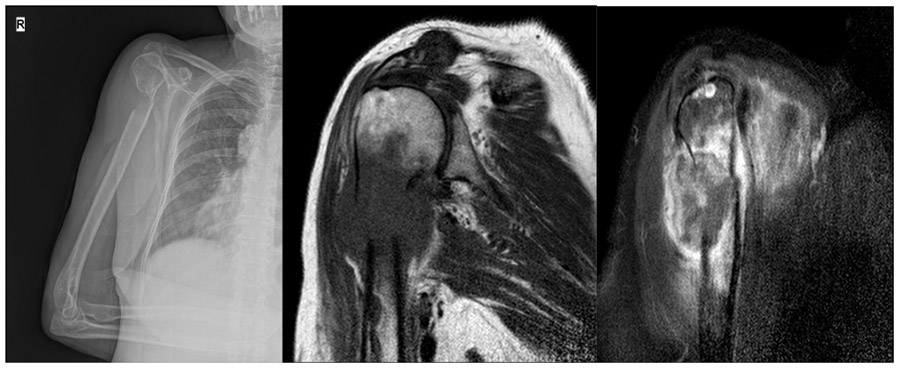

CASE 3: Lung cancer metastasis caused fracture in the right arm (upper end of the humerus) bone.

Before the surgery: X-ray shows destruction and fracture of the superior end of the right humerus, and MRI shows widespread edema accompanied by a metastatic focus extending beyond the bone.